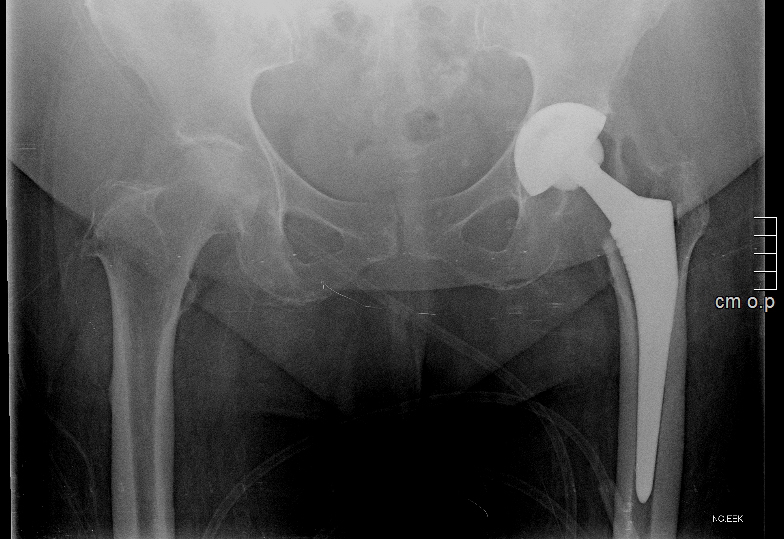

Στις περιπτώσεις που οι ασθενείς με αρθρίτιδα ισχίου δεν βελτιώνονται με τη συντηρητική αγωγή, προτείνεται η χειρουργική αντιμετώπιση με ολική αρθροπλαστική ισχίου. Η συγκεκριμένη επέμβαση έχει χαρακτηριστεί ως μία από τις πιο επιτυχημένες στην ιστορία της ιατρικής, ανεξαρτήτου ειδικότητας. Πρόκειται για αντικατάσταση της άρθρωσης του ισχίου με τη χρήση ενός μηριαίου στειλεού, την τοποθέτηση μιας πρόθεσης στην κοτύλη και τη μεταξύ τους άρθρωση με ειδικό υλικό που περιορίζει την τριβή.

Αρθροπλαστική ισχίου

Η αρθροπλαστική ισχίου μπορεί να γίνει με αρκετές χειρουργικές προσπελάσεις. Η πιο διαδεδομένη είναι σαφώς η οπίσθια προσπέλαση, ενώ πολύ συχνά επιλέγεται η τροποποιημένη κατά Hardinge ή η πρόσθια. Στις σύγχρονες προσπελάσεις ελάχιστης επεμβατικότητας περιλαμβάνονται η SuperPath, η Path, η AMIS και η ALMIS, ενώ πλέον πολλές εξ αυτών συνδυάζονται με συστήματα πλοήγησης ή ρομποτική υποβοήθηση που υπόσχονται ακόμα καλύτερα αποτελέσματα. Η κάθε τεχνική παρουσιάζει πλεονεκτήματα και μειονεκτήματα, ωστόσο η επιτυχής έκβαση της αρθροπλαστικής ισχίου εξαρτάται κυρίως από την ακριβή τοποθέτηση των προθέσεων που θα εξασφαλίσει ομαλή και ανώδυνη κίνηση, ίδιο μήκος στα κάτω άκρα και μακροζωία στα υλικά.

Συνολικά, το αποτέλεσμα της αρθροπλαστικής ισχίου σχετίζεται με πολλούς παράγοντες. Αρχικά από την επιλογή των κατάλληλων υλικών, καθώς υπάρχουν προθέσεις διαφορετικού σχεδιασμού και φιλοσοφίας, ανάλογα με την ανατομία, την ηλικία και τις απαιτήσεις του κάθε ασθενούς. Επιπλέον, καίριας σημασίας είναι η επιλογή της κατάλληλης προσπέλασης και ο ακριβής προεγχειρητικός σχεδιασμός που θα οδηγήσει στο ιδανικό αποτέλεσμα με ασφάλεια. Ο ασθενής πρέπει να είναι πλήρως ενημερωμένος για το πρόγραμμα αποκατάστασης που θα κληθεί να ακολουθήσει, ώστε να έχει από πριν φροντίσει για λεπτομέρειες όπως η πιθανή παρουσία προσώπου για βοήθεια στο σπίτι.